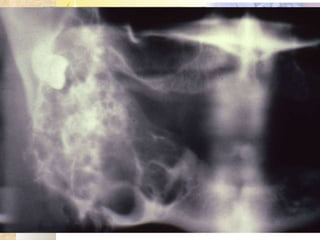

INVESTIGATIONS Radiological – OPG, lateral occlusal mandibular radiograph Complete blood picture, CT, BT Incisional biopsy

Present  radiograph 1 year back

RADIOLOGICAL FEATURES Unilocular radiolucency, especially early lesions that often progress to multilocular ( soap-bubble, honeycomb ) May be associated with impacted tooth Cortical expansion and thinning Resorption of adjacent tooth roots, displacement of teeth can be seen